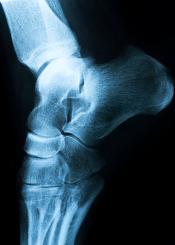

El diagnóstico se basará en la descripción del dolor que haga el paciente. Con una simple radiografía de perfil del pie se puede apreciar la presencia del espolón calcáneo. Por lo general no se requiere realizar ninguna otra prueba complementaria.